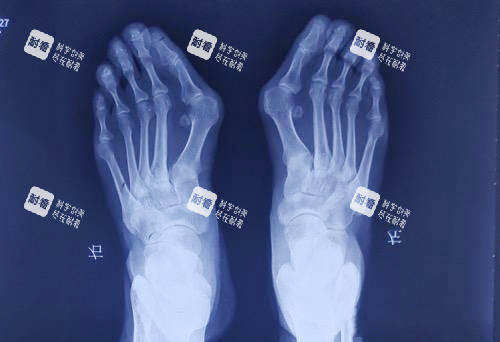

“哎哟喂!这大脚骨一走路就钻心疼,高跟鞋不敢穿,运动鞋磨得慌,连跳广场舞都成了奢望!”北京朝阳区的刘阿姨捂着脚直叹气,她这拇外翻的毛病折腾了五年,试过矫正器、贴膏药,然后还是决定找医生手术。可一打听,苏敬达和马桂文两位医生都挺有名,一个骨科博士,一个27年老医生,选谁?这问题就像“豆腐脑吃甜还是咸”,可把人愁坏了!

马桂文这边,资历更吓人——1995年就开始研究足病,到现在整整27年!他是北京煤医西坝河医疗美容医院的“头牌”,还是马文足医生集团的建立人,手握31项国内专有,其中21项是自己研发的,10项是和北医三院联合搞的。他开展的“5D微孔弧祛大脚骨技术”,用光导仪器实时监测截骨角度,误差小于0.5度,连重度畸形(外翻角>40°)都能精细矫正。